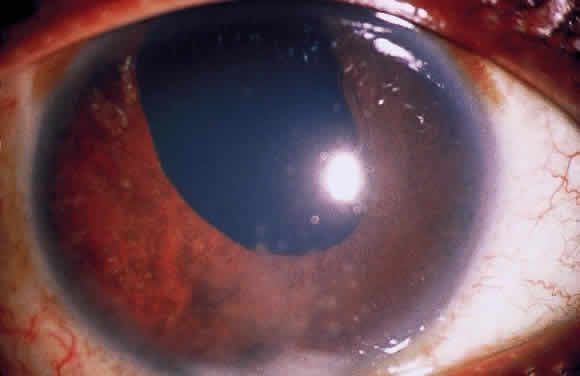

Posterior synechiae may also develop without nodule formation because fibrin in the aqueous can induce adhesions to the lens. Later, fibrous organization may make adhesions pharmacologically unbreakable, and the formation of synechiae during treatment indicates inadequate therapy. If posterior synechia formation proceeds unchecked, pupillary block glaucoma may develop (Fig. 8). Peripheral anterior synechiae (PAS) in the anterior chamber angle may result from chronic shallowing of the anterior chamber because of posterior synechiae and pupillary block. They may also result from fibrous organization of inflammatory exudates and precipitates in the angle. Rubeosis may also occur in severe long-standing uveitis and lead to PAS. Progression of PAS may lead to angleclosure glaucoma.